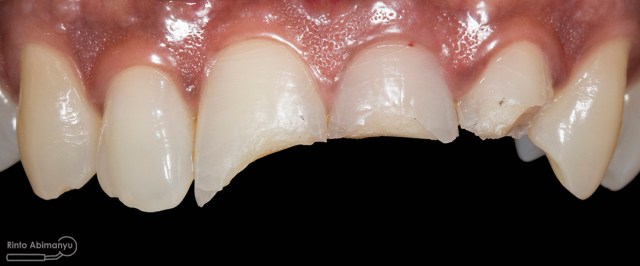

Kasus hari ini tentang gigi-gigi anterior yang fraktur karena kecelakaan lalu lintas. Pasien datang menceritakan kejadian yang dialaminya dan meminta saran bagaimana sebaiknya tindakan yang dilakukan pada giginya…

Begini kondisi klinis saat datang…

Foto klinis gigi-gigi anterior yang mengalami fraktur